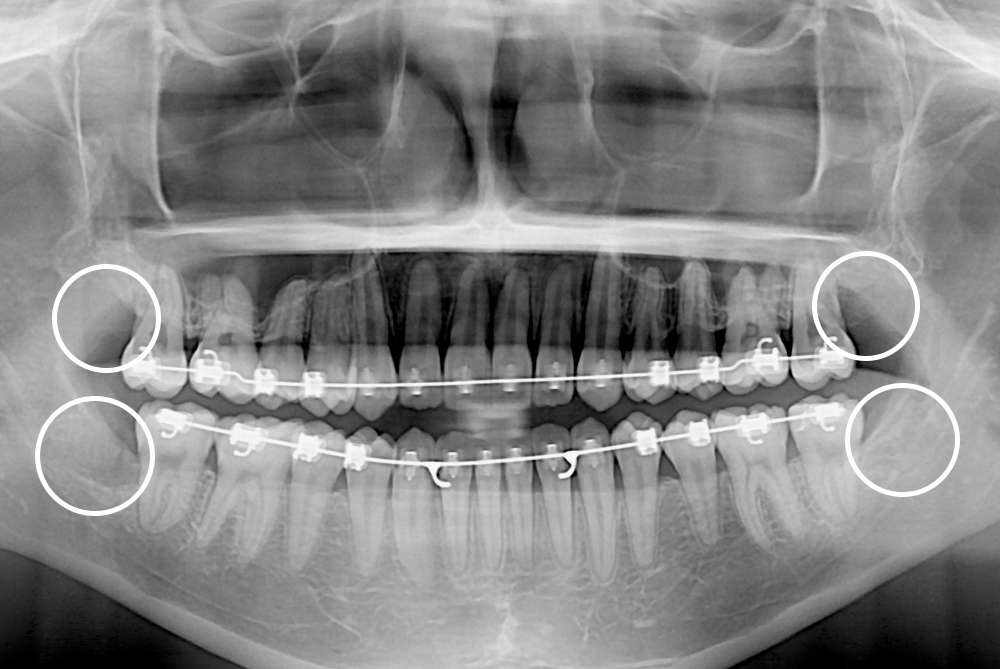

[사랑니] 매복 사랑니 발치

치료후 : 2017-05-09

세종치과는 구강악안면외과학 박사이신 원장님이 발치하는 치과입니다.